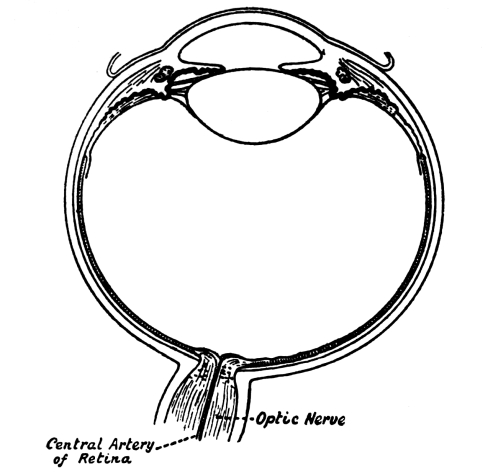

| 27. | Horizontal Section of the Eye | 373 |

| 28. | Development of the Crystalline Lens | 374 |

| 29. | Purkinje’s Shadows of the Vessels of the Retina | 375 |

| 30. | Retina adapted for Obscurity and for Bright Light | 377 |

| 32. | Formation of an Image on the Retina | 391 |

| 33. | The Form of the Eyeball in Short Sight, Normal Sight,and Long Sight | 392 [Pg x] |

| 34. | The Blind Spot | 394 |